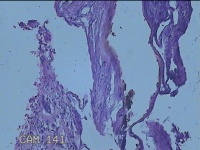

阑尾

临床诊断

急性坏疽性阑尾炎 弥漫性腹膜炎

一般病史

转移性右下腹疼痛3天。

标本名称

大体所见

灰白暗红色阑尾2.5x0.8x0.3cm一条,表面糜烂,肿胀,带大量系膜,部分已切开,见腔内暗红色,另有灰褐色粪石1.9x0.7x0.3m一枚。